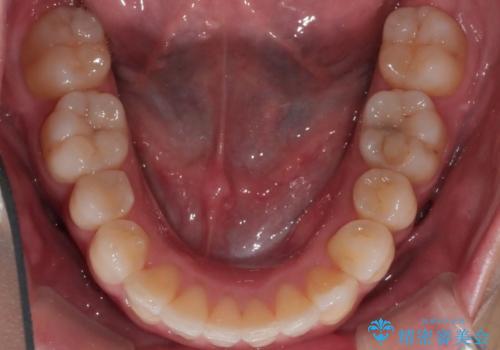

八重歯でがたつきは重度でしたが、きれいな歯並びにすることができました。

がたつきだけでなく、奥歯の噛み合わせのずれの調整もしっかり行いました。

奥歯のずれの調整は時間がかかりますが、矯正後の歯並びの安定度が向上します。